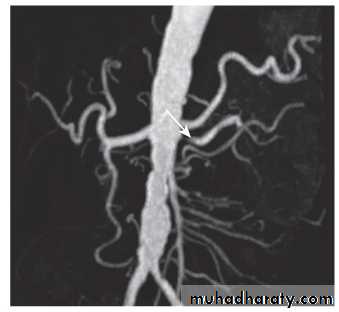

The definitive investigation is renal arteriography, but this carries the risk of contrast nephropathy, and significant additional risks in patients with severe atherosclerosis. Non-invasive angiographic techniques such as MR angiography and spiral CT angiography are being increasingly used. MR angiography is expensive and limited in availability. CT angiography entails large, intravenously administered doses of contrast medium which may be nephrotoxic.

Although these techniques can at present give good views of only the main renal arteries, these are the vessels affected in atherosclerosis and are most amenable to intervention. Given the expense and possible risks, angiography should only be undertaken in patients in whom intervention to improve renal perfusion would be contemplated. This is usually limited to young patients and those in whom blood pressure cannot be controlled with antihypertensive agents ('resistant hypertension'), those who have a history of 'flash' pulmonary oedema or accelerated phase ('malignant') hypertension, or those in whom renal function is deteriorating.